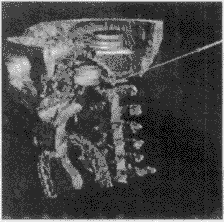

2.4 结果显示

对手术方案的结果进行三维显示和多剖面显示是可视化的关键。系统考虑到各种显示方法的优缺点,对它们进行合理的运用和改进。对医生勾画的重要功能区采用面向多边形的表面显示算法,重建出的区域立体感强,图7是对医生勾画的眼球、视神经和脑干的重建结果。对于颅骨的显示,系统采用了直接投影的体显示法和改进的Marching Cube算法两种,后一种算法可弥补前一种算法对光照效果的过分依赖,而前一种算法则可弥补后一种算法过长的前处理时间的不足,供医生依情况选择,图8、图9为两种算法的显示结果。对于外皮肤的显示,系统综合利用面向多边形的显示方法和面向体素的表面显示方法,首先将构成外皮肤的所有像素自动提取出来,然后利用面向多边形的表面显示方法形成外皮肤,显示的图像比采用Marching Cube算法显示的更细腻、平滑,图10为显示结果。图11为一个复合显示结果。

, 百拇医药

图 7 勾画区域的三维重建(上下为不同角度)